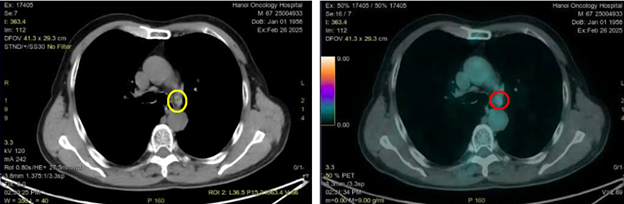

Hình 5: Hình ảnh hạch trung thất ở cửa sổ chủ phổi đường kính 7 mm trên CT (vòng tròn màu vàng) và PET/CT (vòng tròn màu đỏ) tăng chuyển hóa FDG (SUVmax: 2,69)

Hình 6: Hình ảnh CT cấu trúc bình thường (bên trái) và hình ảnh tăng hoạt tính phóng xạ ở xương ức trên PET/CT (vòng tròn màu đỏ) (SUVmax: 18,1)